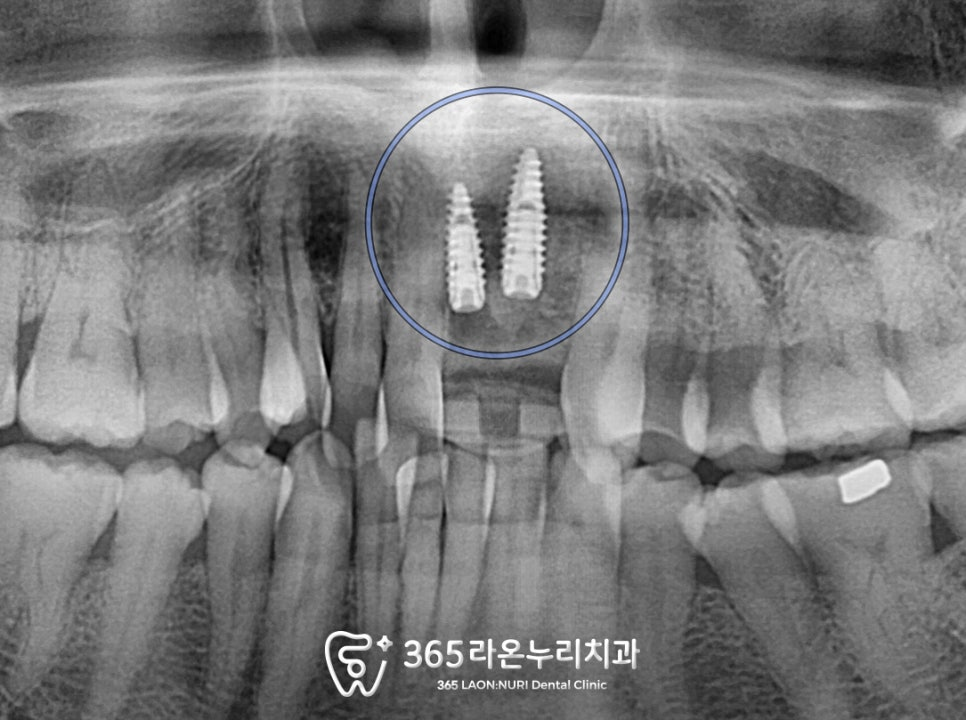

오산세교 치과 에서

사진을 확인해 보면

2025.01.05

21번 치아는 치관파절로 절반이

부러진 상태였고 22번 치아는

발치된 모습을 확인할 수 있습니다.

이가 뿌리만 남고 다 부러졌고,

남아있는 뿌리마저도 다 쪼개져 있어서

안타깝게도 이는 살릴 수 없어 보였습니다.